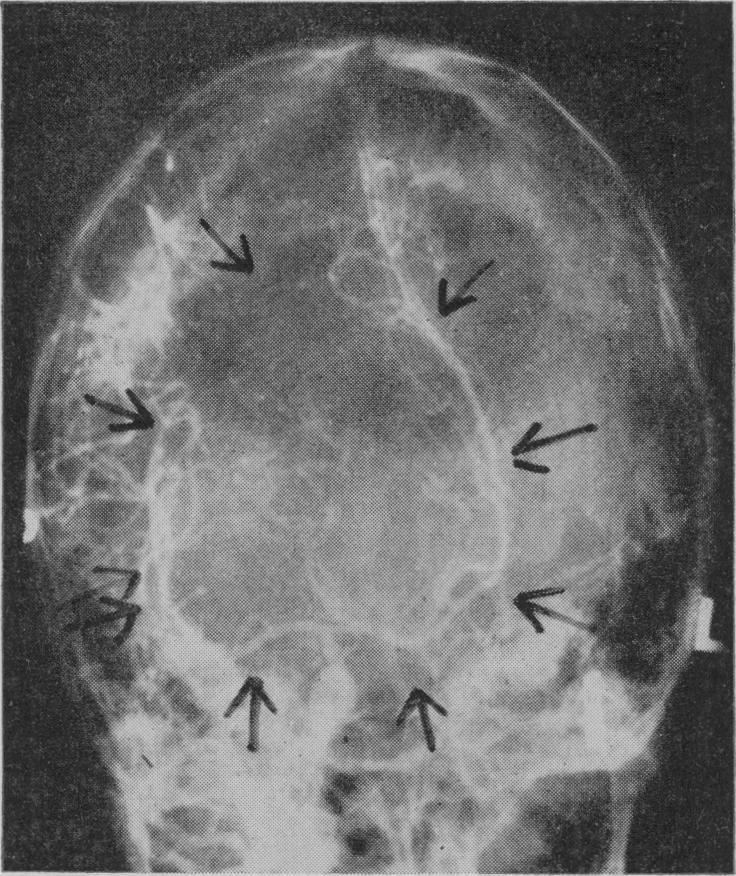

Cerebral abscess presenting as larceny.

Proc R Soc Med. 1960 Mar;53(3):225-6. doi: 10.1177/003591576005300316.